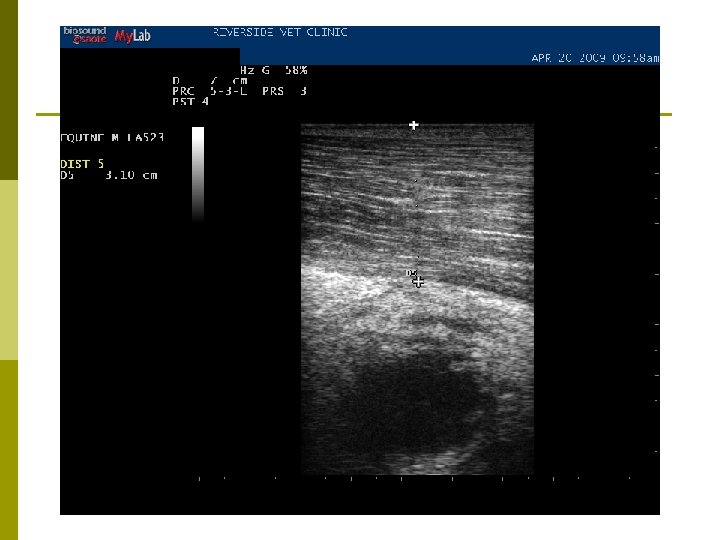

Diagnosis p Index of suspicion p Culture n Gold standard p Ultrasonography p Serology n Internal abscesses

Ultrasonography

Treatment p Time n n “You want me to. . . wait? !” Yeah… p p lets allow the abscess to “cook” for a bit Drainage n Ultrasound guidance p Determine vascularity, depth, site